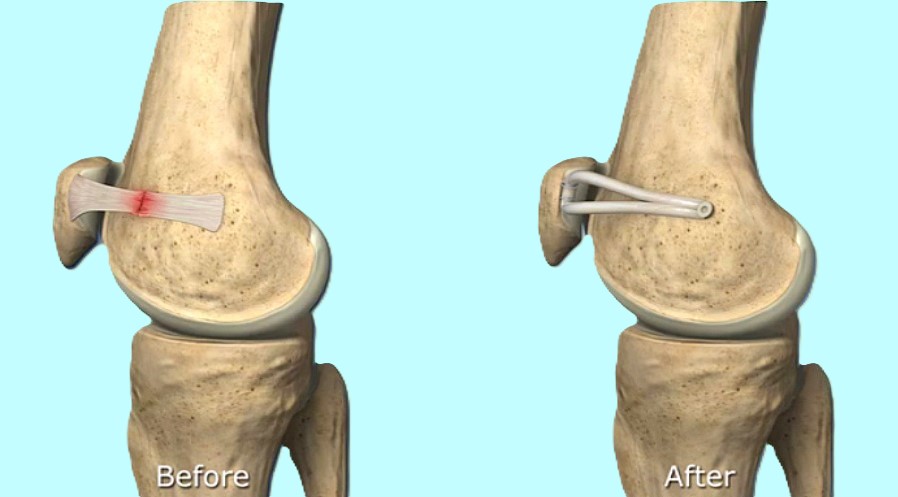

膝蓋骨脱臼

横浜整形外科クリニック野村医師は膝蓋骨脱臼に重要な内側膝蓋大腿(MPFL)靱帯を発見し解剖の教科書に書かれていなかったMPFL靱帯を1990年に世界で初めて発表しました。

その後膝蓋骨脱臼に対するMPFL再建術を開発し長年にわたり国内外で研究発表をしてきました。現在野村医師の研究したMPFL再建術は世界的に広く行われています。

膝蓋骨脱臼は軽い例から重度の例まで症例により大きな違いがあるため、安易に手術を行うと結果に大きな差が出てきます。従って術前に十分検討する必要性があります。

また初回脱臼後長い間経過すると軟骨障害がひどくなるため早めに手術する必要があります。本手術は野村医師の治療をお薦めします。

膝蓋骨脱臼の概説

横浜整形外科クリニック野村院長は30年以上にわたり膝蓋骨脱臼について研究してきました。

1990年に世界で最も早くに内側膝蓋大腿靱帯(medial patellofemoral ligament:MPFL)を発見し解剖学的研究を発表しました。MPFL再建術も世界で最初に報告しています。それ以来国内外で100以上の学会発表や和文英文論文を発表してきました。

1999年に『膝蓋骨脱臼における内側膝蓋大腿靱帯再建術損傷形態』によりSICOT国際学会賞を受賞しました。2000年以後世界的にMPFL再建術の研究が進み、2005年以後はMPFL再建術は世界の標準的手術となりました。

現在までに野村医師の膝蓋骨脱臼手術例は500例以上になり世界一です。野村医師は膝蓋骨脱臼における世界的権威です。

膝蓋骨脱臼治療の歴史

反復性膝蓋骨脱臼の治療は1950~1990年代まで、外側解離術・内側広筋前進術/内側縫縮術・脛骨粗面移行術が主な手術法(過去の手術)でした。

初回膝蓋骨脱臼の治療は関節内血腫を除去しギプスや副木固定を行うのが主体でした。しかし『どの損傷に固定が必要なのか』の基本的疑問さえ明確な答えがないまま治療が行われてきました。

ギプスの治療で十分であるとした過去の治療法が平均13年もの長期的研究(Maenpaa1997)により疑問が呈されました。初回膝蓋骨脱臼の保存的治療で満足できたのはわずかに33%のみでした。

長期的成績が多く報告されるようになり成績の不安定さとともに多くの問題がわかってきました。膝蓋骨脱臼の手術法が100種類以上もあることは裏を返せば、この疾患の本質がわからなかったことを示すものだったのです。

野村医師は日本および世界で最も早くの1990年にこの手術法を開発報告し、2000年頃より世界でこの手術法が急速に広まり、2005年からは世界の標準的手術となっています。

野村医師は世界で最も長期の報告も行い内側膝蓋大腿靱帯の安全性と有用性を立証しました。

世界的雑誌AJSMのSystematic review(Buckens 2010,AJSM)によると、MPFL再建術の2009年以前の世界の論文から信頼できる論文は12個のみでありその内野村医師は2000年に世界で最初に信頼できる論文を発表し12個の内3個の野村医師の論文が選ばれています。

野村医師は日本のほぼ全ての教科書の反復性膝蓋骨脱臼項目について執筆しており、世界的権威となっています。

内側膝蓋大腿靱帯(MPFL)再建術

横浜整形外科野村院長は世界で最も早く膝蓋骨脱臼に対するMPFL再建術を開発し現在まで500例以上の手術を行ってきました。この数は世界トップクラスです。

再建材料として1997年まで人工靭帯法、1998年に自家腱法を開発しました。手術結果は世界的雑誌 The Knee、Arthroscopy、AJSMに4つ論文が掲載されました。採取する腱の半腱様筋腱や薄筋腱は採取しても運動機能に影響はありません。人工靱帯法でも組織学的に良好な靱帯が再生されることが判明しています。世界的雑誌AJSMのレビュー(Bucken 2010,AJSM)ではMPFL再建術の2009年以前の世界の論文から信頼できる論文は12個のみであり、その内野村医師は2000年に世界で最初に信頼できる論文を発表したと記載されています。12個の内3個の野村医師の論文が選ばれています。

2022年最新手術法開発

術後スケジュールは手術2~4日目に杖なしで退院・術後リハビリ通院不要・ランニング2ヶ月~、スポーツ3ヶ月~。世界で最も早いリハビリを達成。

膝蓋骨脱臼の進行や軟骨障害

膝蓋骨脱臼で初回脱臼後10年以上になると、脱臼力も強くなり軟骨の障害例が多くなります。軟骨障害が進むと元通りに回復させることは難しく脱臼は治っても軟骨の痛みが残りますので早めに手術を受けて下さい。初回の脱臼の平均は14~18歳頃ですので手術せずに30歳代になるとこのような状態になります。